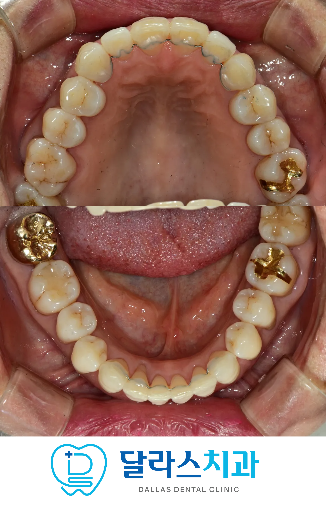

어금니 교합은 안정적으로 물리고 있는 상태이면서

안모가 특별하게 돌출이 있거나 하지 않았기 때문에

노원치과에서는

Mini Tube Appliance(MTA)를 이용한

상하악 전치부 부분교정을 계획하였습니다.

위아래 앞니 각각 6개씩, 총 12개의 치아에만 장치를 부착하여 치료를 진행하였습니다.

MTA를 활용한 전치부 부분교정은

불필요한 치아 이동을 줄이고 앞니 배열 개선에 집중한 것이 특징입니다.